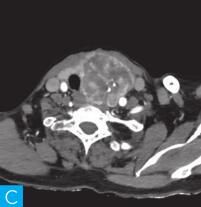

甲状腺CT检查:CT检查设备为256层iCT,病人采取仰卧位,扫描范围自外耳道平面至下颌角以下,常规扫描层厚为0.9mm、层间隔0.9mm,电压120kV,管电流280mA,矩阵512×512;经右肘静脉团注法增强扫描,碘海醇80ml,流速4ml/s,动脉期25秒扫描,静脉期60秒扫描。见图1。

图1 甲状腺CT

A、B.甲状腺CT横断面平扫;C~H.甲状腺CT横断面增强

答案C 解析:该病灶病史时间长,无发热及疼痛;病变位于一侧甲状腺,边界清楚;甲状腺血流及静态显像示:甲状腺左叶较大“凉”结节。因此不考虑恶性肿瘤及感染性病变。病变强化特点为结节状改变,呈现肿块样,故考虑肿瘤样病变。

CT平扫可见甲状腺左叶圆形以低密度为主病灶,大小为8.0cm×6.5cm,边界清晰,边缘尚光整,其内密度不均匀,低密度区CT值18HU,部分密度稍高,并可见斑点状粗大钙化影;CT增强后,甲状腺左叶病变呈不均匀渐进性强化,结节状改变,动脉期强化区CT值99HU,静脉期CT值85HU,且强化范围增大,提示该病变的血供较为丰富,应该考虑肿瘤样病变,结节性甲状腺肿可能性大。

本病例CT扫描发现起源于甲状腺较为容易,但要观察病变是囊性、实质性或囊实性及其供血,CT增强扫描十分必要,易于显示囊实性病变及其供血情况,其结节状改变更加显著,有助于判定病灶的血液供应情况。本病例基本征象为类圆形、边缘清晰、内粗大钙化、结节状强化之肿块。